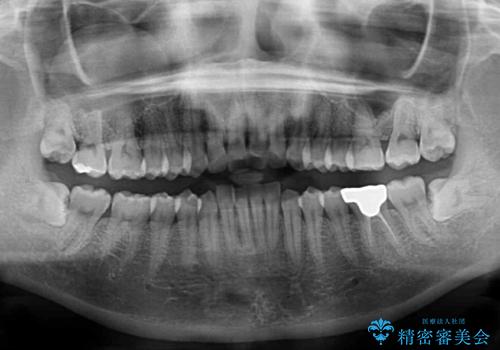

- 上下の前歯のデコボコを気にして来院された患者様です。

妊娠中であり、途中通院が難しくなる可能性があることから、インビザラインによる矯正治療を行うこととしました。

上下顎歯列全体の後方移動とIPR(歯と歯の間を削る)によってデコボコが解消するように設計しました。